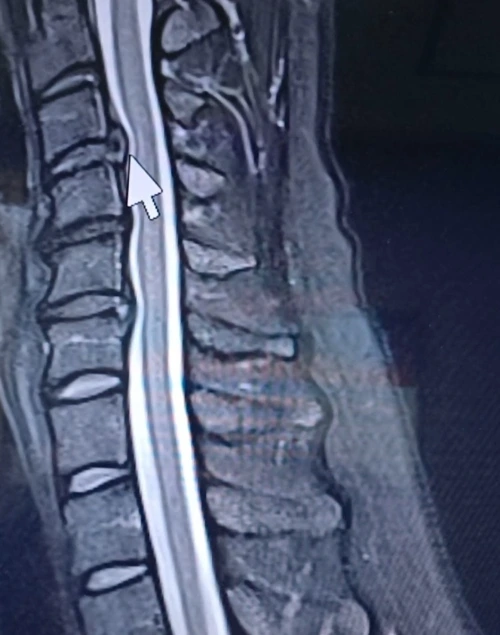

꼬리뼈는 그간 치료 덕인지 아니면 목 통증이 더 강해서인지 잘 느껴지지 않았다. 결국 CT는 찍지 않았다. 영상을 설명하던 의사는 화살표를 가리키며 말했다.

“원래는 추간판 탈출증인데, 일자목이라고들 하죠. 좀 심하네요. 수술이 필요할 수도 있어요. 자세한 건 정형외과나 재활의학과에서 상담해 보세요.”